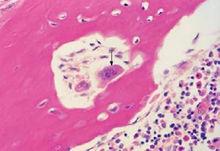

骨原細胞(osteogenitor cell)位於結締組織形成的骨外膜及骨內膜貼近骨組織處。細胞較小、梭形、核橢圓、胞質少。骨原細胞為骨組織的幹細胞,隨著骨生長、改建、分化為成骨細胞。